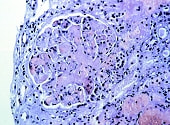

抗リン脂質抗体とは、細胞膜を構成する成分のひとつであるリン脂質、またはその結合タンパクに対する抗体のことをいいます。この抗体がある人は、動脈や静脈の血管が詰まる( 血栓症)、 妊娠をしても 流産や死産を繰り返す、血小板が減少する、といった病態が起こりやすくなります。このようなケースにつけられる診断名が、「 抗リン脂質抗体症候群」です

全身性エリテマトーデスなどほかの膠原病がもとにあり、それと併発して起こることも多く、その場合は「 続発性杭リン脂質抗体症候群」といいます。また、もとになっている膠原病がなく、単独で起こることもあり、このような場合は 「原発性抗リン脂質抗体症候群」と分類されます。